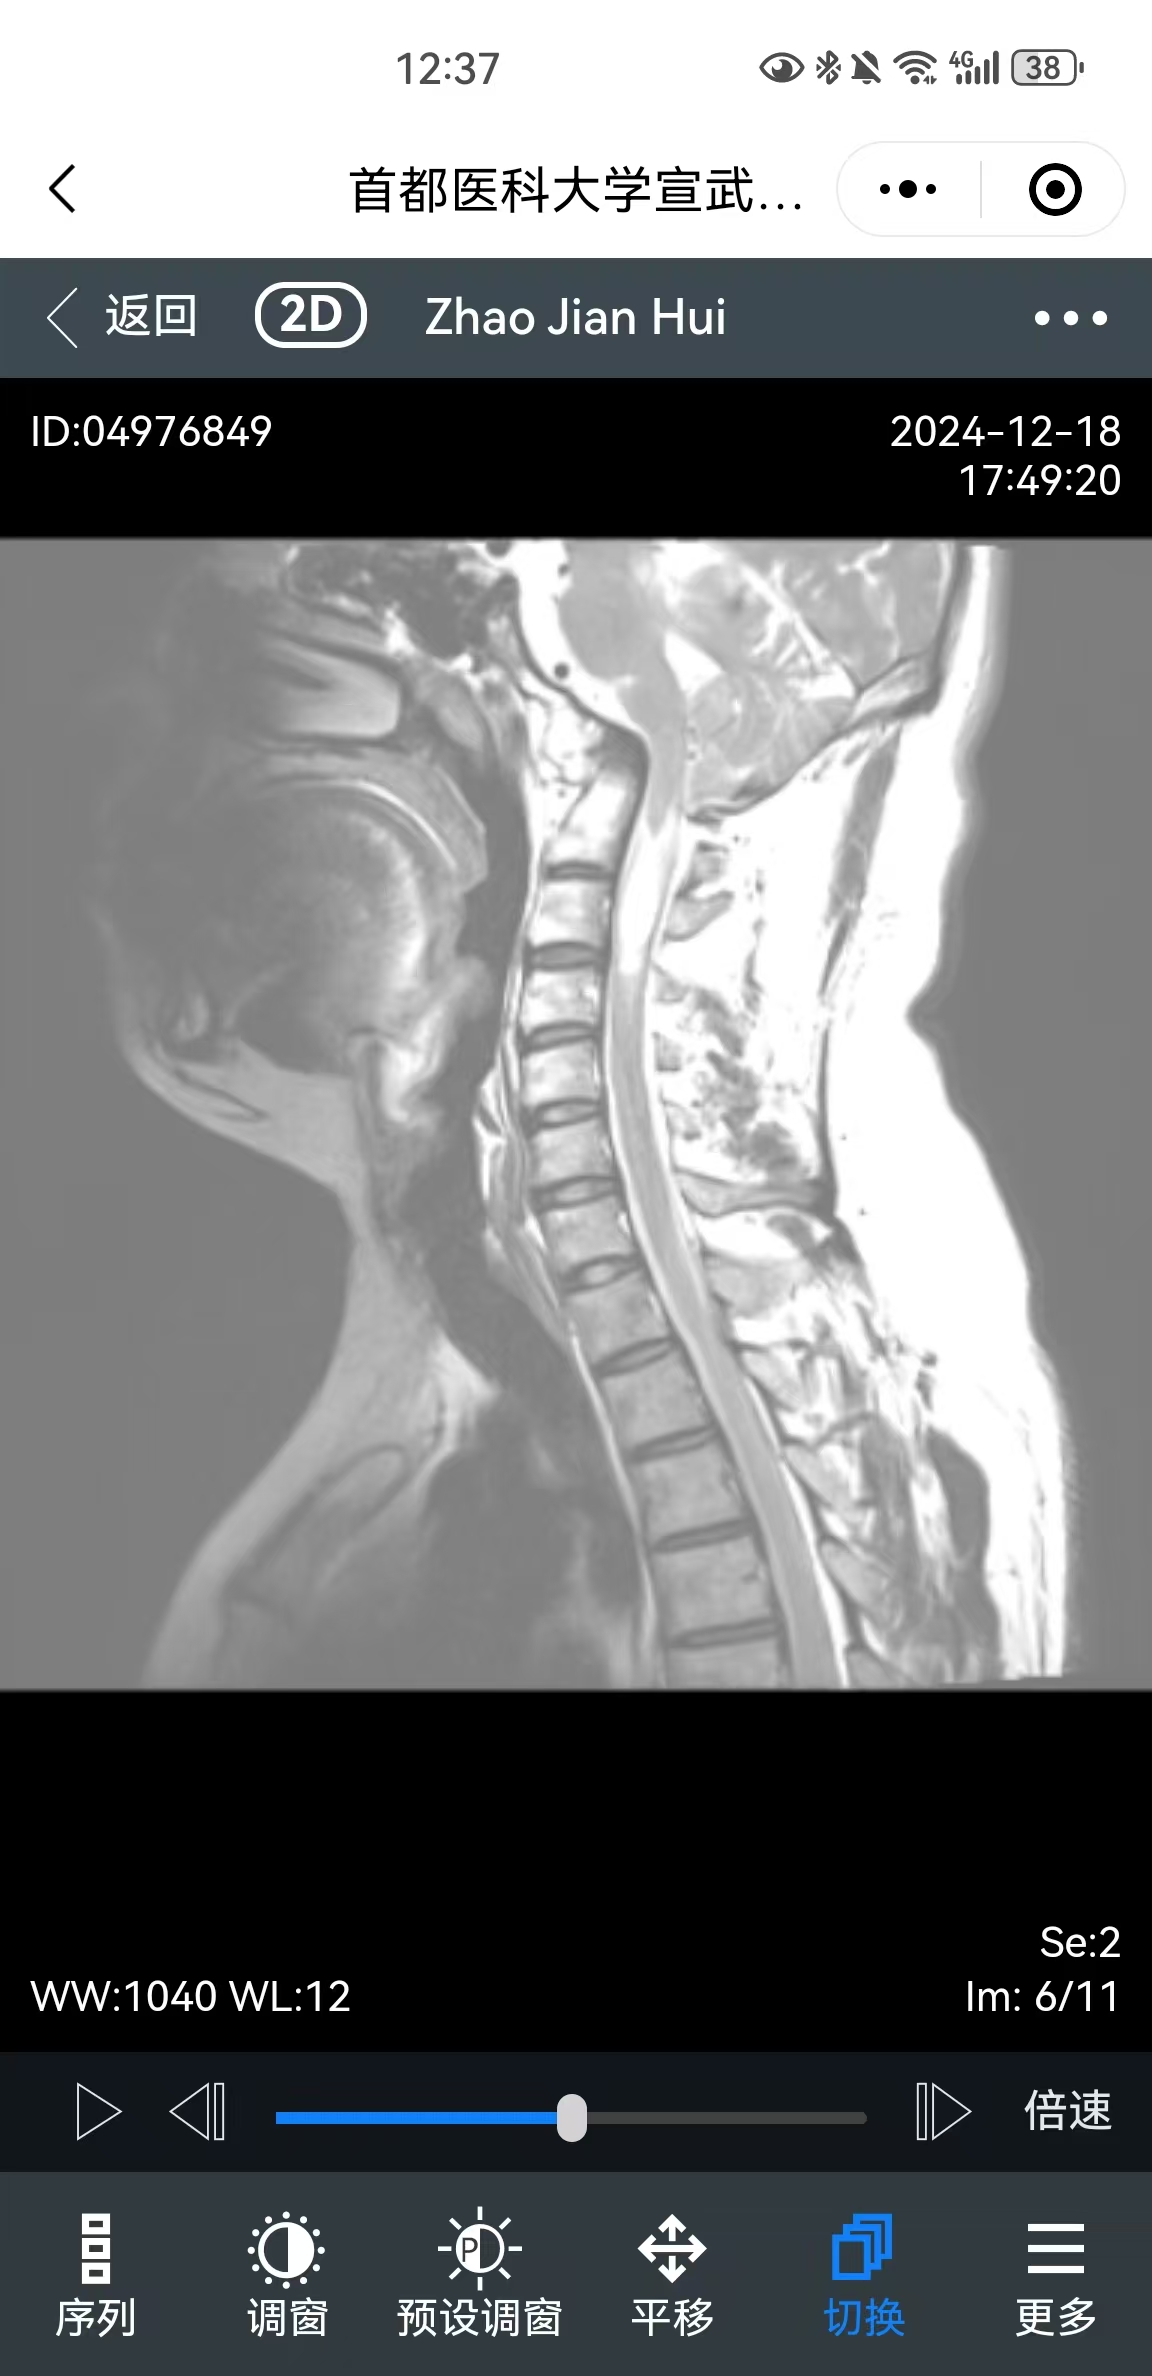

• 影像:

• 术后影像: